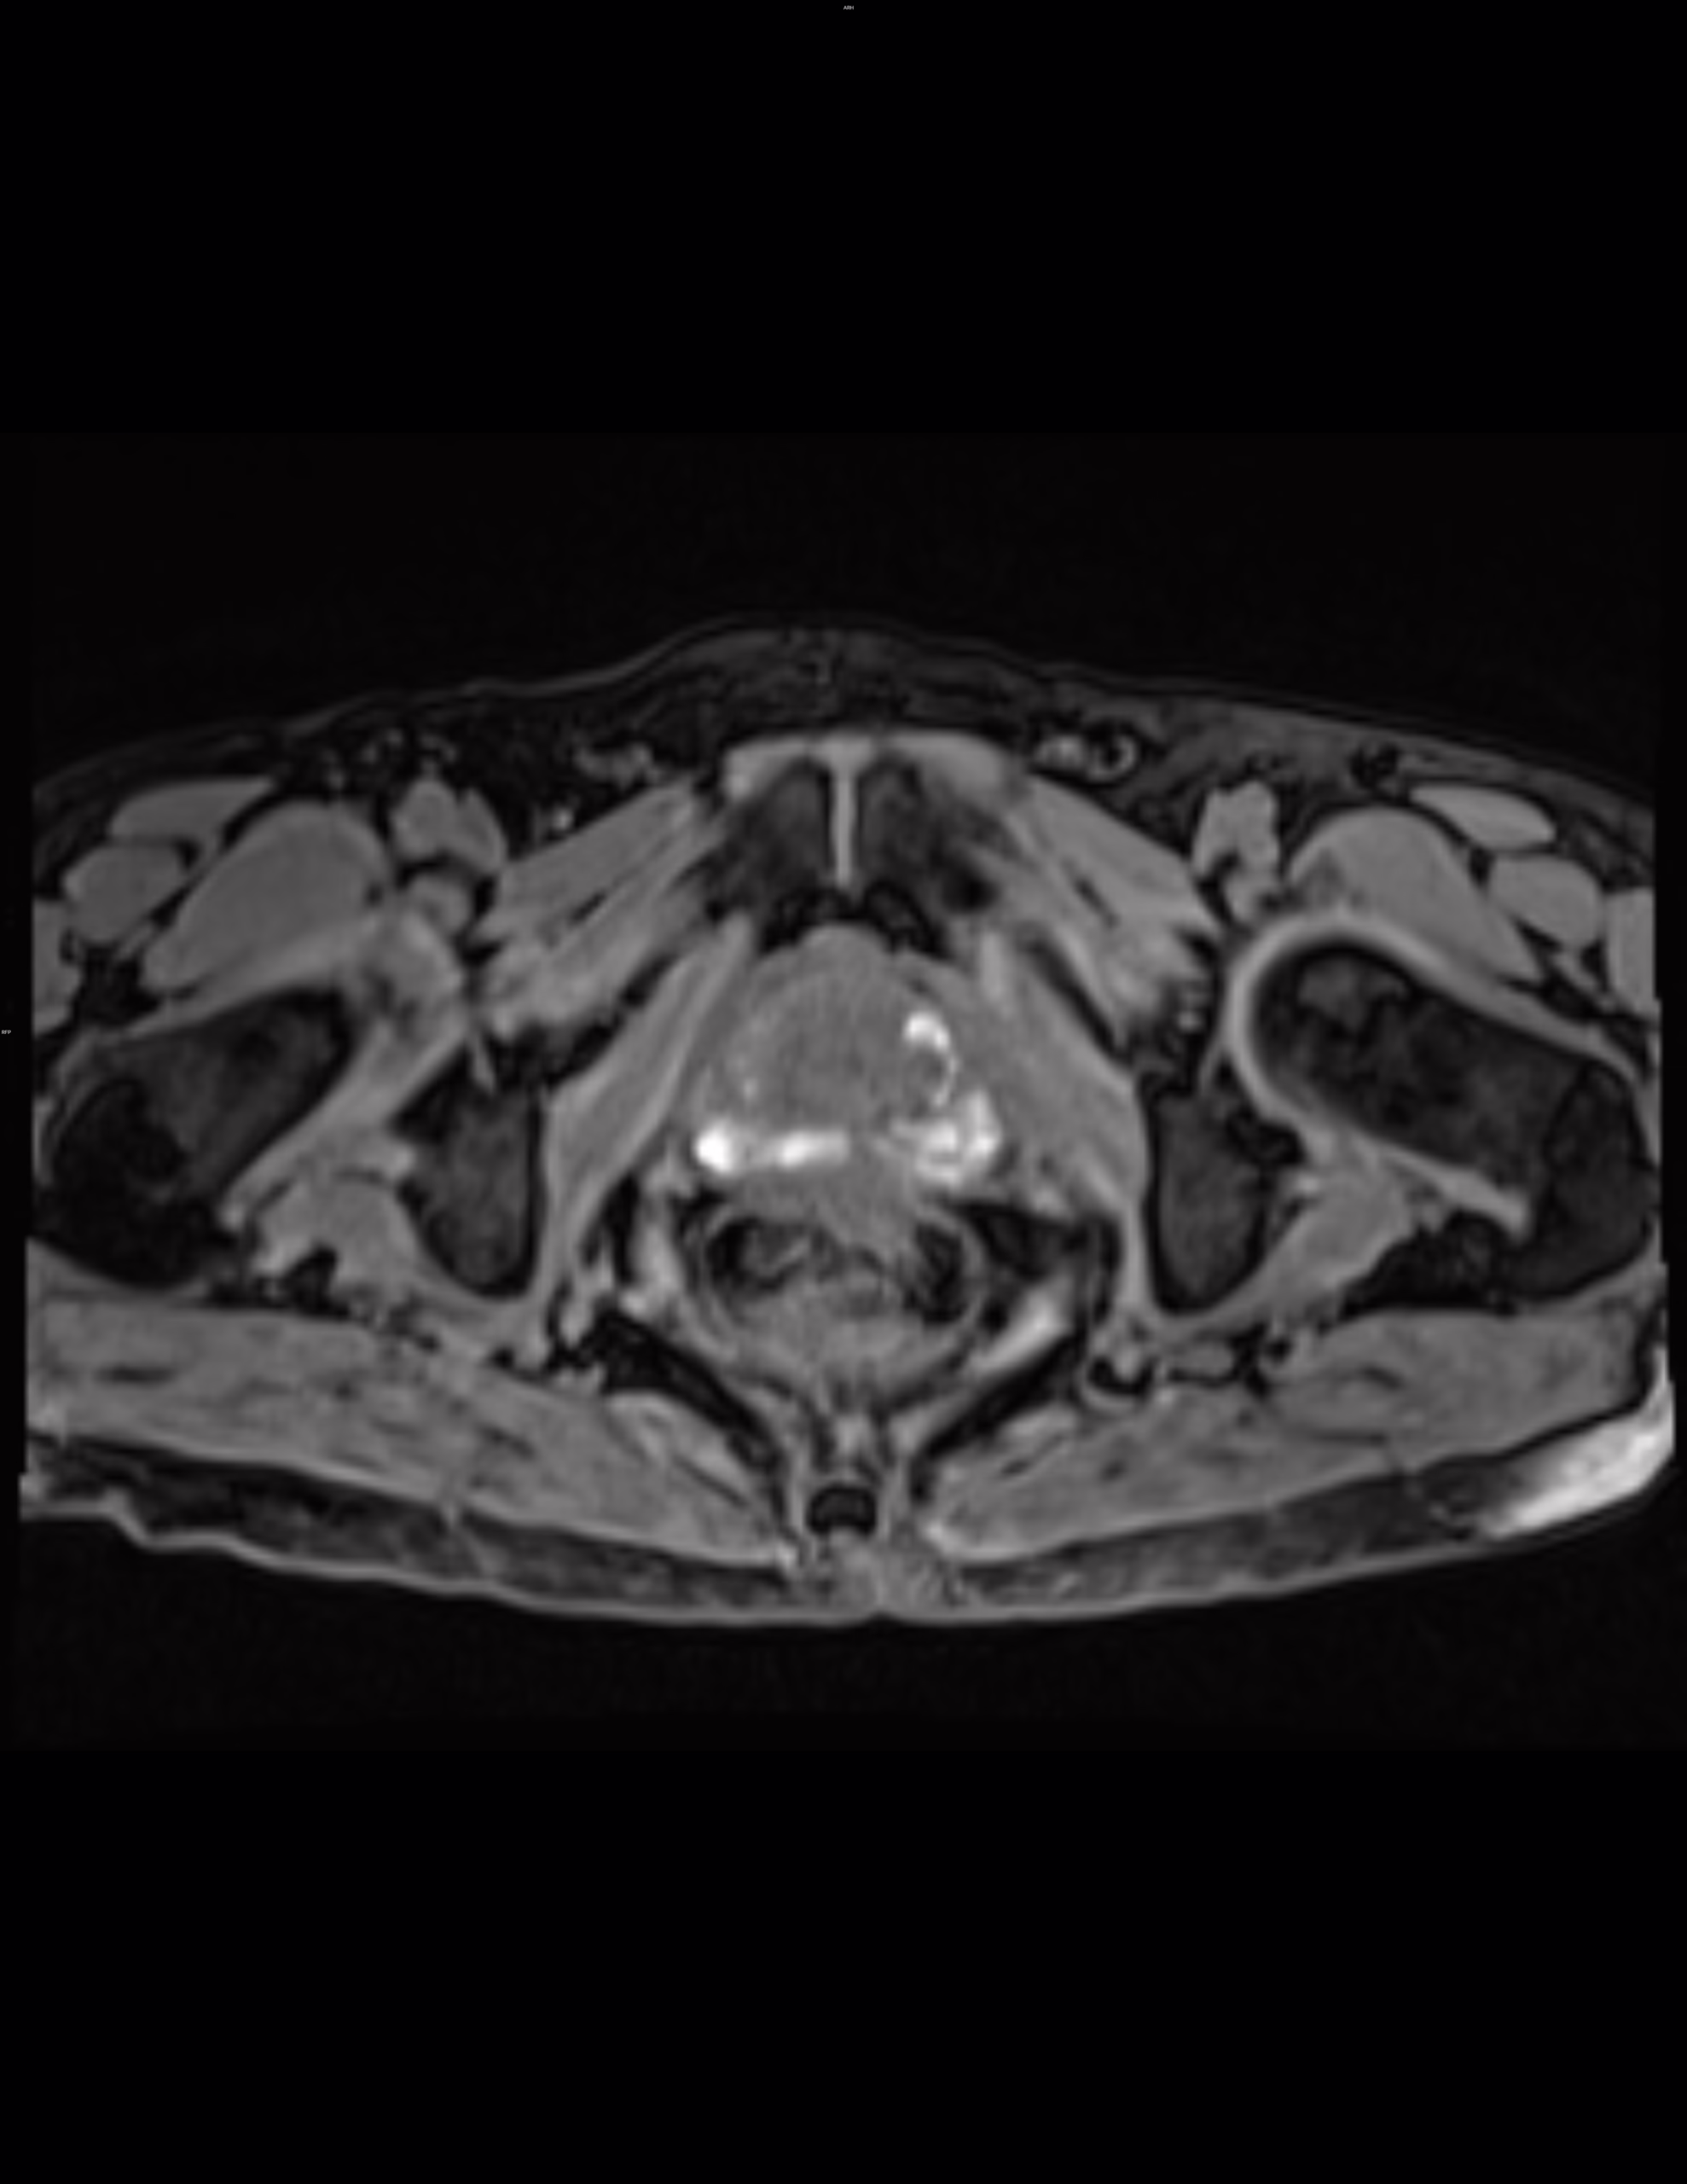

Método de estudio: Resonancia magnética de próstata en secuencias multiplanares en imágenes ponderadas en T2 axial, sagital y coronal, difusión, mapa de ADC, T1 axial, T2-FATSAT e imágenes de contraste dinámicas después de la administración IV de gadolinio.

Se observan cambios por hipertrofia prostática con patrón de crecimiento tipo III (transicional bilateral y retroureteral), con protrusión del lóbulo medio hacia el piso vesical en 12 mm (IPP grado 3).

Se favorece engrosamiento de la pared vesical en relación con cambios por vejiga de esfuerzo (mide 8.4 mm de AP).

Se identifican cambios hemáticos dispersos en ambas zonas periféricas evidentes hiperintensidades difusas en secuencia T1 y T1-FATSAT, no muestran restricción hídrica en difusión, relacionado con antecedente conocido.

En ambas zonas transicionales destacando del lado izquierdo a nivel anterior y medial corresponde a un nódulo hiperplásico de contornos definidos que muestra cambios hemáticos como hiperintensidad en T1 y T1-FATSAT.

Vesículas seminales: simétricas, distendidas, sin alteraciones.